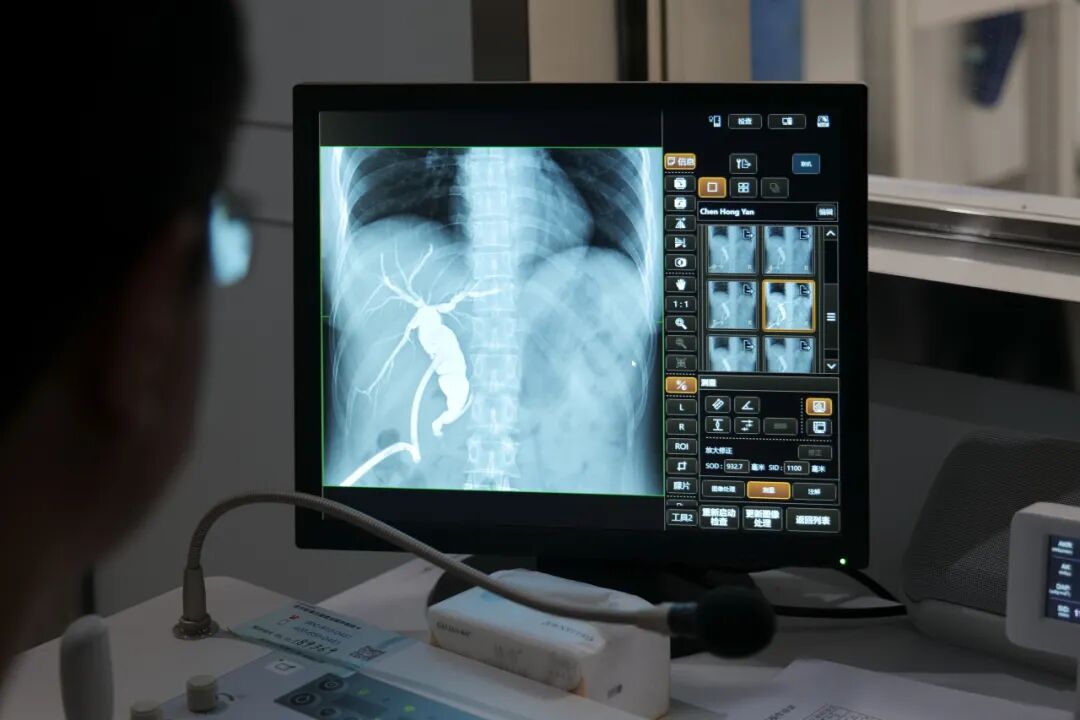

呼吸系统:

既可胸部DR也可在透视下直接胸部数字点片;